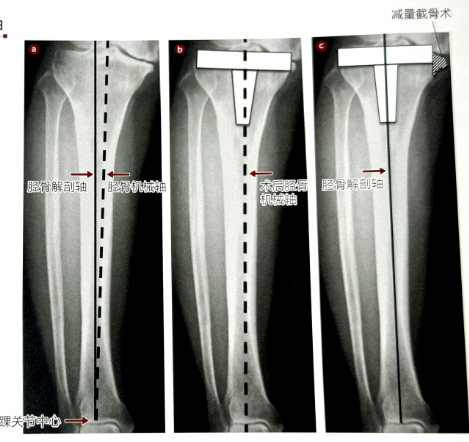

冠状面(正面)轴线设置定位的基本轴是指术后胫骨机械轴(连接踝关节中央和术后胫骨假体中央的连线)和胫骨解剖轴(胫骨轴)(图5a在没有胫骨内翻的病例中,这两根轴是一致的,但是在胫骨出现内翻的病例中,这两根轴并不一致,所以必须考虑将胫骨近端垂直于哪个轴后再进行截骨。而且,在术野中正确地鉴别踝关节中央的位置并不是件容易的事。推荐的方法有:将胫骨远端1/4的前方皮质隆起的胫骨作为踝关节中心的替代方法;将髓外导向器的正面对准胫骨前后轴之后,将胫骨对线器的踝钳固定于踝关节内、外踝隆起处,其中点作为踝关节的中心点等。

图片

图5 胫骨的机械轴和解剖轴

a:胫骨机械轴和解剖轴存在胫骨内翻时有差异。

b:在术后机械轴上垂直设置胫骨假体的方法。

C:在胫骨解剖轴上垂直设置假体的方法。

术后胫骨机械轴垂直设置的方法:

在设置假体模板时,选择**限度地覆盖胫骨近端截骨面的假体尺寸,试模的轴指向踝关节中央设置(图5b。尽管采用此法胫骨残留内翻畸形甚至在术后仍然保持,但是MCL不需要松解。HKA(髋-膝-踝角)角度为0。如果在有胫骨内翻的情况下**限度地覆盖截骨面,截骨面与胫骨解剖轴垂直设置,相对于术后机械轴,胫骨假体呈现过度外翻,需要MCL松解的病例较多。所以多使用胫骨截骨导向器。

与胫骨解剖轴垂直设置的方法!在胫骨内翻很严重的病例中,为了使胫骨解剖轴与假体柄的轴一致,除了尺寸缩小以及假体外移(图5c。因为假体的未覆盖部分是在胫骨平台内侧可以在相同部位实施截骨(内侧髁缩小截骨术)。而且切除该部分后可缓解MCI张力,从而避免 MCL松解过多。采用这种手术操作,术后胫骨机械轴与胫骨解剖轴一致,胫骨内翻消失。与术前计划预定的一样,将截骨髓外导向器的近端固定位置、髓内截骨导向器的骨髓内杆插入位置从髁间隆起间略微向外移动。无论选择以上哪种方法,都是相对于术后机械轴垂直地设置假体。但是:前者可以选择较大的假体尺寸,但残留胫骨导致一定程度的膝内翻;后者可以消除胫骨内翻,但假体尺寸较小。在胫骨内翻严重的病例中,胫骨假体大小决定股骨假体的尺寸,股骨假体相对于股骨远端缩小一个尺寸,也有采取将两者折中之法进行设计的。尽可能减轻胫骨内翻的同时,与术后机械轴垂直设置是比较好的。